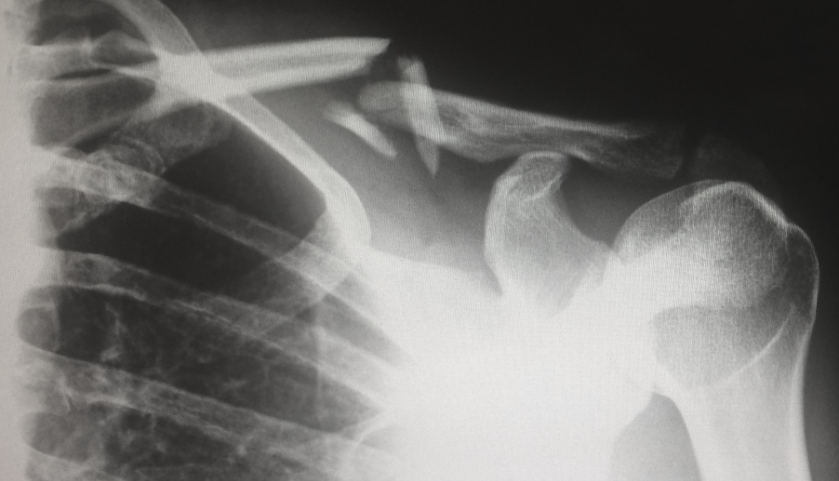

人工关节分为膝关节和髋关节, 其中膝关节置换手术占到带量采购手术台数的43%左右,而髋关节置换手术占到57%左右。人工髋关节则是根据球头和髋臼杯的材质不同分为陶瓷-陶瓷、陶瓷-聚乙烯、合金-聚乙烯三类。而陶瓷-陶瓷、陶瓷-聚乙烯、合金-聚乙烯三类产品的主要区别体现在力学性能和生物学性能上。